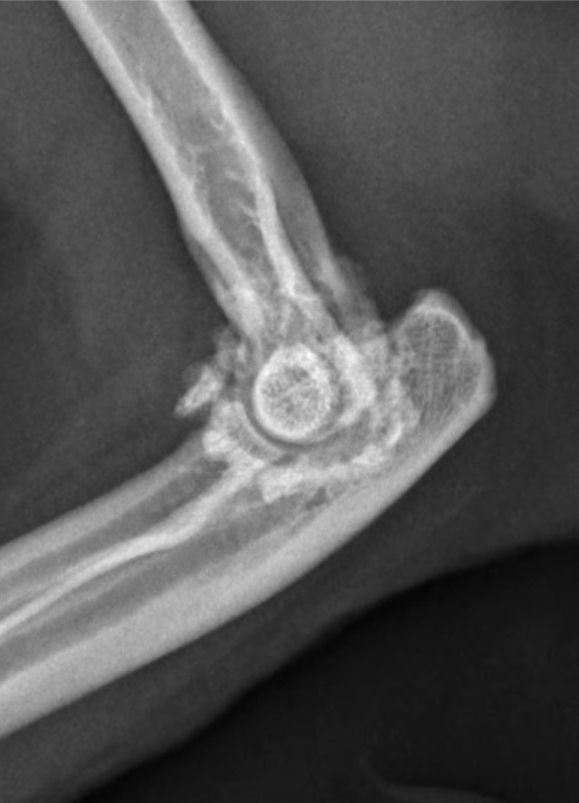

Radiografia

Apesar de suas limitações, a radiografia continua sendo o método mais utilizado para diagnosticar a osteosteoartritertrite em gatos, devido à sua ampla disponibilidade e percepção de custo-efetividade. No entanto, é amplamente reconhecido que a radiografia só é capaz de detectar osteoartrite em estágios avançados ou graves [16]. As características radiográficas observadas no diagnóstico da osteoartrite felina incluem a presença de osteófitos, aumento da opacidade do osso subcondral, mineralizações intra-articulares e de tecidos moles, espessamento dos tecidos moles e efusão sinovial (Figura 3). Quando alterações degenerativas são observadas nas radiografias, as mudanças degenerativas histológicas confirmam a presença de osteoartrite com alta especificidade [16].

No entanto, a radiografia é uma modalidade de imagem bidimensional, o que significa que alterações fora das estruturas esqueléticas ou próximas às bordas podem não ser facilmente visíveis [16]. Além disso, é impossível visualizar a cartilagem por meio de radiografias, e os achados radiográficos não estão bem correlacionados com a degeneração da cartilagem; um estudo constatou que até 71% das articulações femorais felinas com evidências macroscópicas de osteoartrite não apresentavam lesões associadas nas radiografias [17]. Essas limitações reduzem a eficácia da radiografia na detecção precoce ou leve da osteoartrite. De fato, um estudo recente observou que a radiografia não conseguiu detectar nenhuma articulação diagnosticada com osteoartrite leve histologicamente [16].

Apesar das limitações, a radiografia muitas vezes é a única modalidade de imagem disponível e, portanto, sua interpretação deve ser otimizada. Ter consciência de onde e do que procurar facilitará o diagnóstico precoce. O desenvolvimento de osteofitose pode ser mais lento em gatos do que em cães [2],[4], e outros sinais radiográficos, como diferentes tipos de formação óssea, podem ter uma relevância maior [17]. Embora os osteófitos sejam frequentemente considerados a principal característica radiográfica da osteoartrite, em felinos isso só parece ser verdade para a articulação coxofemoral [17],[18]. Para o cotovelo, tarso e joelho, as características radiográficas mais comuns são, na verdade, mineralizações associadas à articulação, proliferação óssea dorsal do tarso-metatarso e mineralizações intra-articulares, respectivamente [17]. Portanto, é essencial examinar minuciosamente as radiografias das articulações felinas em busca dessas outras formações ósseas ao redor das articulações e estar atento aos sinais de crescimento de osteófitos. Além disso, é fundamental lembrar das limitações da radiografia no diagnóstico precoce da osteoartrite. Quando há suspeita dessa condição, mas os sinais radiográficos não são evidentes, é importante buscar modalidades de diagnóstico mais sensíveis.

b

Figura 3. Imagens representativas demonstrando as alterações radiográficas comumente associadas à osteoartrite felina. Na visão ventrodorsal dos quadris (a), pode-se apreciar a formação de osteófitos nas margens acetabulares craniodorsais, além do remodelamento das cabeças femorais. Na visão mediolateral do cotovelo (b), pode-se apreciar um aumento da opacidade óssea subcondral na região peritrocilar, além da formação de osteófitos periarticulares. Na visão mediolateral do joelho (c), pode-se apreciar mineralização intra-articular e efusão sinovial. © Karen Perry